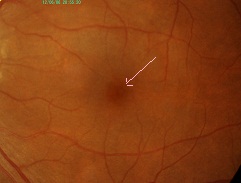

?黄斑円孔で、赤の部分の網膜が硝子体に引っ張られて断裂し、無くなってしまうと、視野の中心部が欠損、見たい部分が見えなくなってしまいます。

中心部の視野がごくわずか。

中心部の視野がごくわずか。